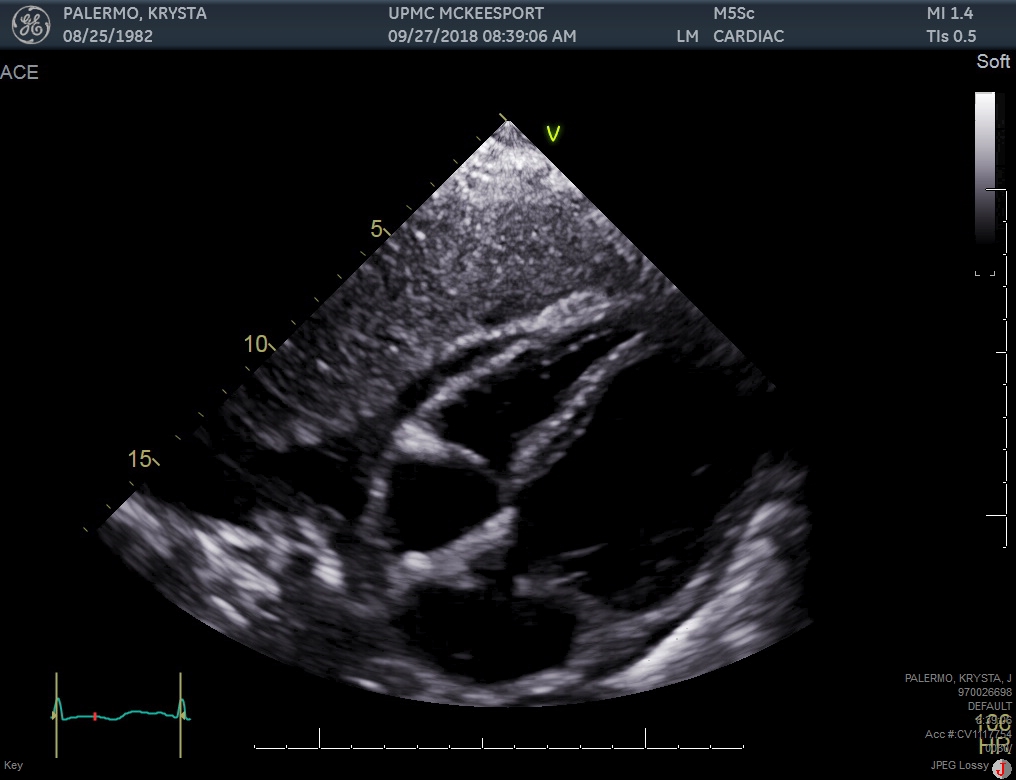

Case Presentation: A 36 years old female with past medical history of IV drug abuse, presented with dyspnea, nasal congestion, tactile disturbances, diarrhea, body aches and generalized weakness for 1 day. She was recently treated for tricuspid valve endocarditis. A Transthoracic Echocardiogram (TTE) obtained at that time showed ejection fraction (EF) of 55-60%. On presentation, vital signs were remarkable for tachycardia and tachypnea. Physical examination demonstrated bibasilar crackles and peripheral edema. ECG showed sinus tachycardia. Chest X-ray revealed pulmonary edema. CT angiogram did not show any pulmonary embolism or septic emboli. Her laboratory findings included BNP of 1070 pg/ml and troponin elevation of 2.030 ng/ml. Urine drug screen was positive for opiates and benzodiazepines. Infectious disease workup was negative. TTE revealed reduced EF of 10-15% and wall motion abnormalities consistent with apical ballooning and hypokinesis of basal segments of left ventricle. InterTAK diagnostic score was 85, showing 99% probability of takotsubo cardiomyopathy. Cardiac catheterization was done that did not show critical coronary artery obstruction. Left ventriculogram revealed apical ballooning with preserved contraction of the base of the ventricle. The patient was diagnosed and treated for heart failure due to takotsubo cardiomyopathy caused by opiate withdrawal. Repeat TTE after 3 weeks showed EF of 55-60% and complete resolution of wall motion abnormalities.